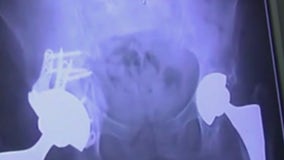

Warning signs for hip problems

If you are having trouble bending or tying your shoe, you may need to visit a doctor sooner rather than later. The Fox Medical Teams' Deena Centofanti joined Good Day with more on the warning signs you need to watch out for.